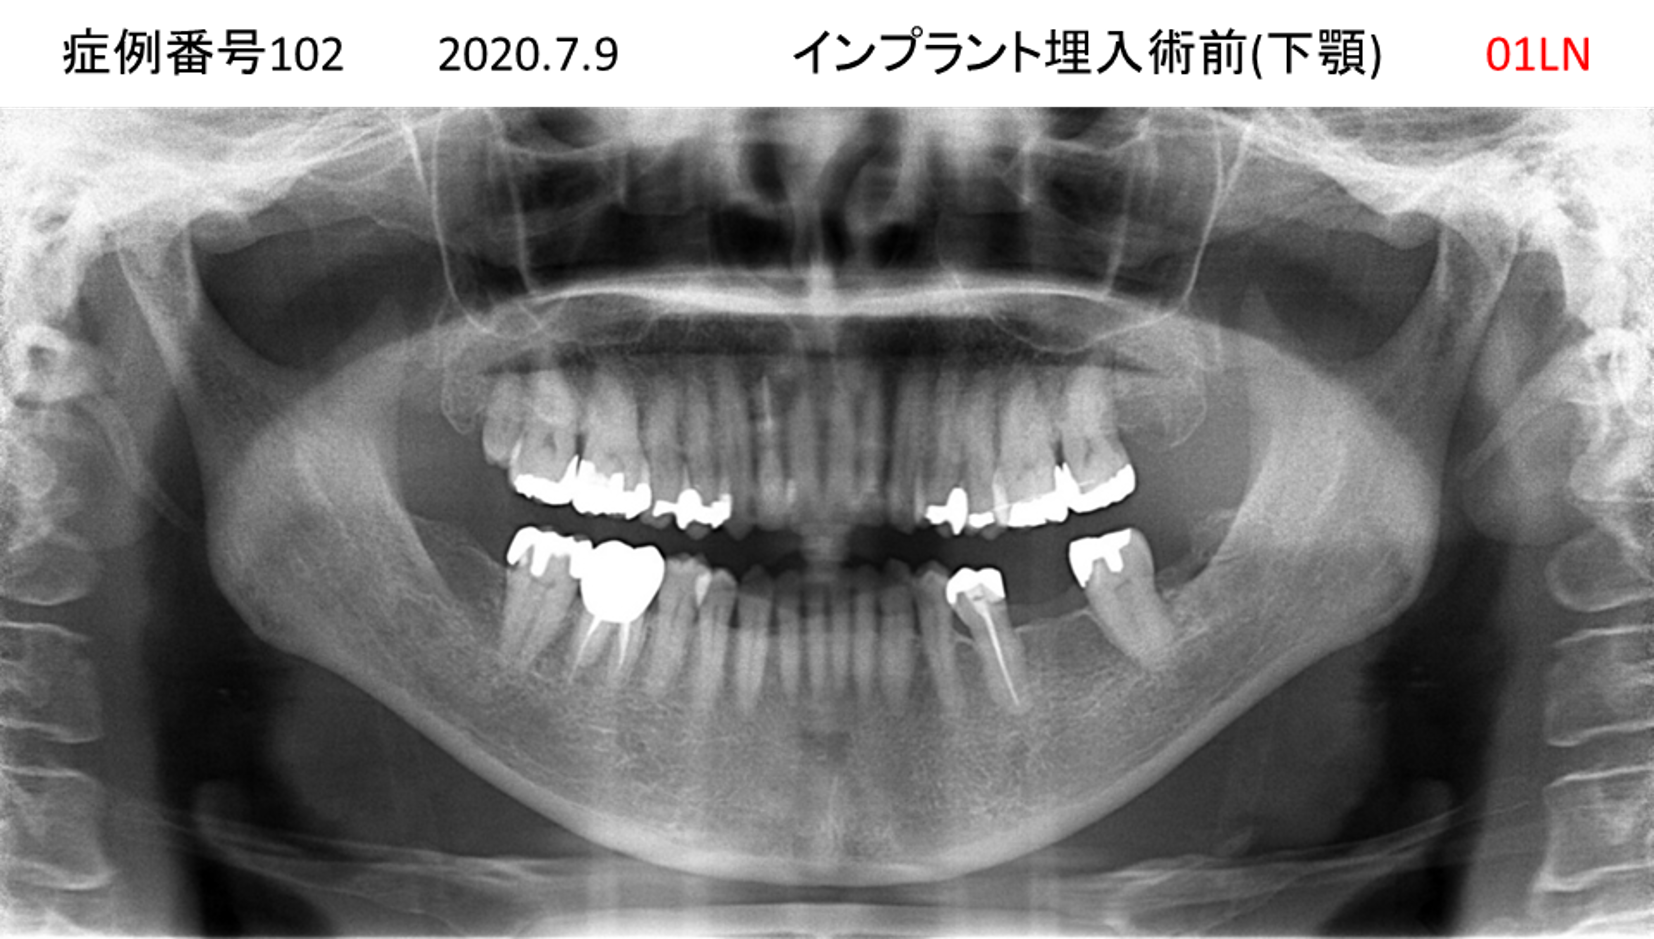

奥歯で噛めない患者様のインプラント症例

| 治療名称 |

インプラント |

| 治療費用 |

365万円+税 |

| 治療期間 |

5か月 |

| 患者さんの症状(主訴) |

奥歯で噛めない。上の前歯が揺れてきた。 |

| 治療内容 |

抜歯即時インプラント |

| 治療結果 |

食事に困らない。見た目がとても良くなった。 |

| 治療の注意点(リスク/副作用) |

インプラントが壊れたら再治療が必要 |